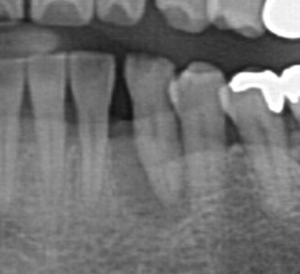

こちらがそのレントゲンです。歯の周りに黒い影があり、歯の根の周囲まで感染が広がっています。

今回の治療は抜歯を行い、3ヶ月待ってから骨の再生を促す処置(GBR:Guided Bone Regeneration)を行いました。

上記の写真が歯周病にて細く、溶けてしまった状態です。

奥歯も歯の根の周囲まで骨が壊れてしまったところをインプラントにて治療したレントゲンです。